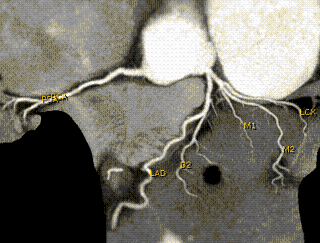

Picture of heart arteries obtained with a multislice CT scanner

The image, above, of the heart arteries was obtained using a special fast XR machine (Multislice CT scanner). The solid white wavy lines are the arteries of the heart. The right heart artery is seen to the left. The left artery and its multiple branches are seen to the right of the image. In this particular instance, there was no significant disease of the heart's arteries.